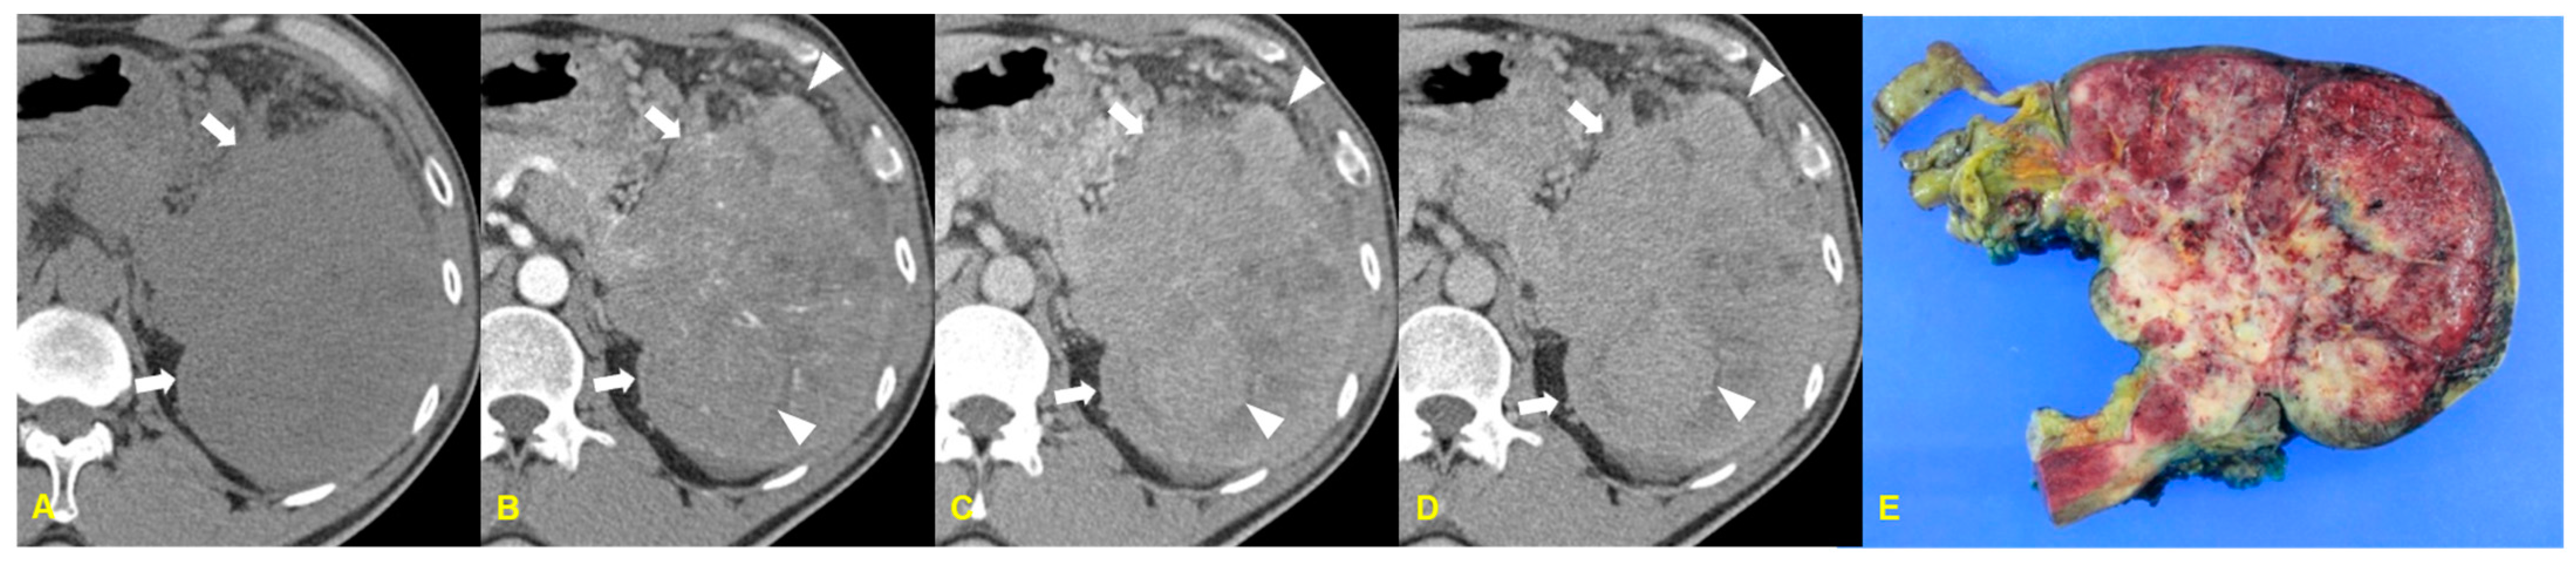

4. Pancreatoblastoma

4.1. Imaging Finding

4.2. Differential Diagnosis

| Pancreatoblastoma | Well defined and lobulated mass with heterogeneous enhancement/Calcification (±)/ Large tumors without invasion of surrounding structures |